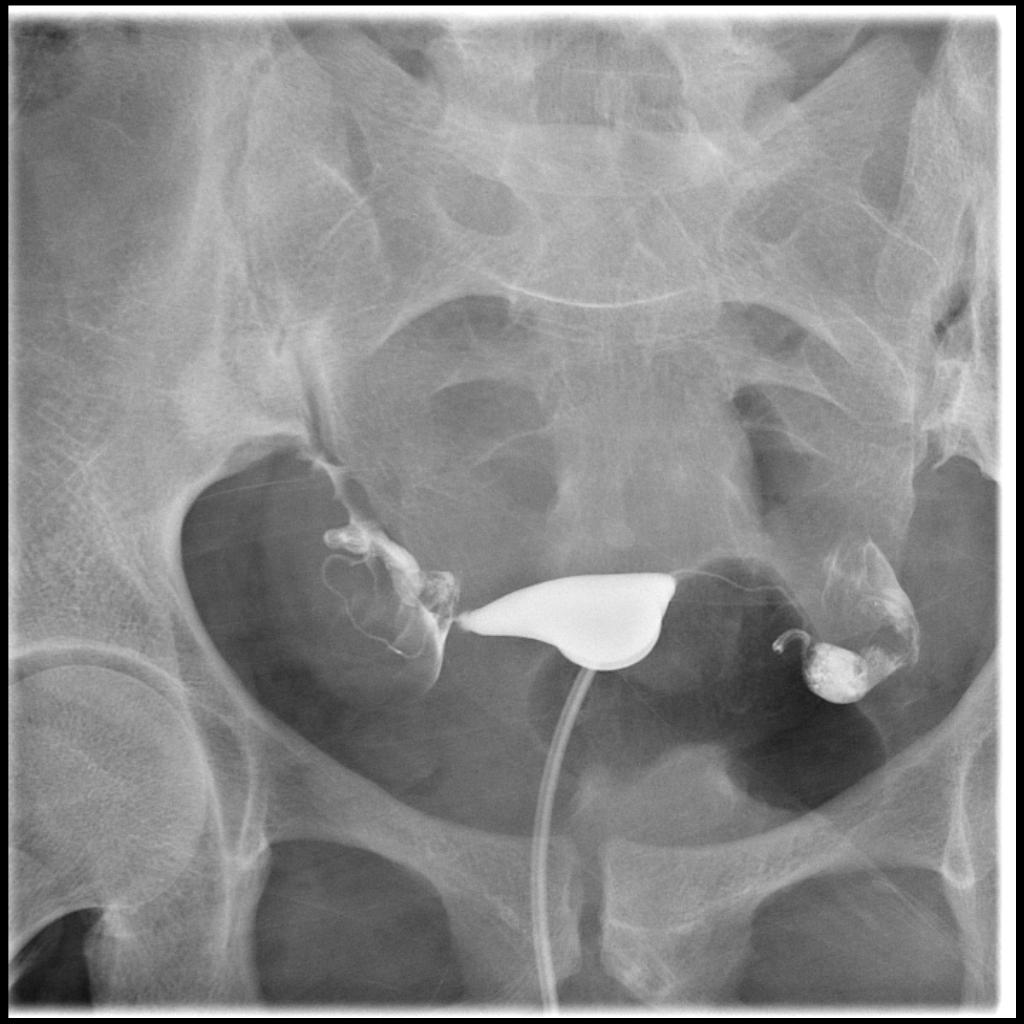

Hysterosalphingogram is a special type of diagnostic X-ray procedure done by the Fertility specialists to find out the tubal factor Infertility of Female Infertility issues. Hysterosalphingogram is also known as Uterosalphingogram. This X-ray procedure is done to ensure both Fallopian tubes are patent (open) and the uterine cavity has a proper shape. HSG is done after a Woman completes her monthly periods but before 12th day of her periods to avoid interference with the Ovulation. Sometimes it may be performed to Women who have suffered from repeated Pregnancy loss to find out the structural abnormalities of Uterus. According to research 30-45 % of Infertility is caused by tubal factors. We at Sakthi Fertility provide HSG X-ray test in Udumalpet, Coimbatore at very low affordable cost. This procedure is done by our Fertility specialists and it takes around 30-45 minutes for this procedure.

This examination is usually done on an outpatient basis. The patient is made to lie on their back with bent knees on an X-ray table like a Gynaecological exam. The speculum is inserted into the vagina to look the cervix and it is cleaned and a catheter is inserted into the Cervix. The catheter is connected with the syringe which contains the dye. Then the dye is pushed into the Uterus. If the tubes are patent, the dye will be released into the other ends of the tube and the Fluoroscopic images are taken immediately after the dye is pushed into the Uterus.

In some cases, if certain abnormalities are encountered, the patient will be asked to take rest and wait up to 30 minutes, so that a delayed image can be obtained. This delayed image may provide clues to a patient's condition that the original images with contrast material do not. On occasion, an X-ray will be taken on the next day to ensure that there is no scarring surrounding the ovaries. When the procedure is complete, the catheter will be removed and the patient will be allowed to sit up. Other abnormalities, if any, are clearly visible from the X-ray images.